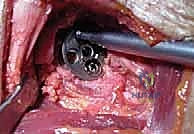

Additional Intraoperative Imaging & Surgical Steps